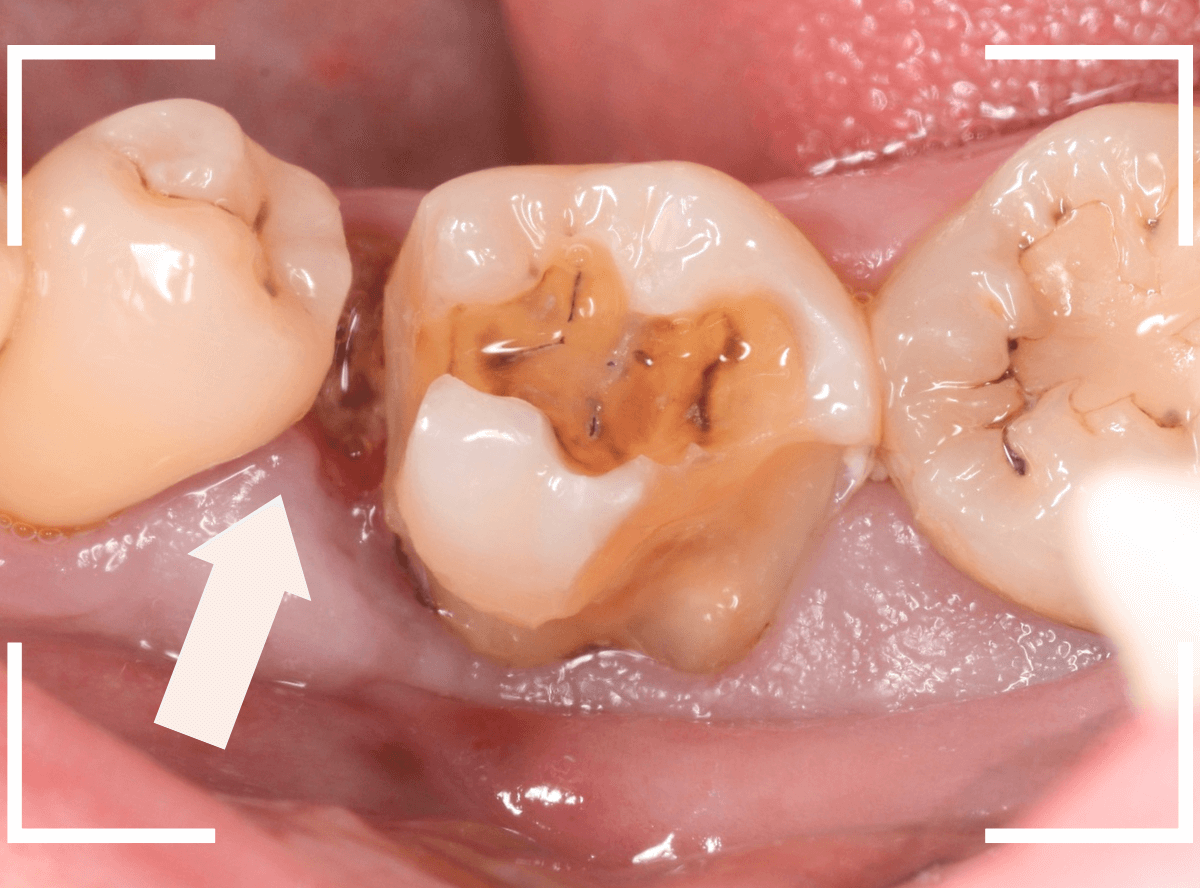

Case.8 抜歯をしながら、虫歯の治療をしたケース

下の奥歯が大きな虫歯になってしまった患者さんです。

レントゲンを撮ってみると、手前の歯との間に歯の根っこが埋まっています(乳歯?)。

虫歯の治療と一緒に抜歯をする必要があります。

レントゲン写真から、左の矢印の部分が大きな虫歯になっていると思われる部分で、右の矢印の歯肉に歯の根っこが埋まっていると思われる部分です。

ほっぺ側にレジンがつまっている事もあり、上から見ただけだとよくわからないですね(><)

表側から見た所です。